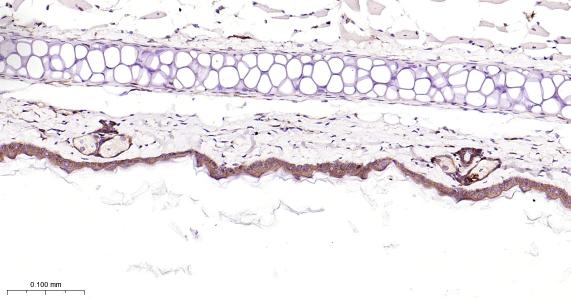

Paraformaldehyde-fixed, paraffin embedded Human abdominal skin; Antigen retrieval by boiling in sodium citrate buffer (pH6.0) for 15 min; Antibody incubation with EGFR Monoclonal Antibody, Unconjugated(bsm-52317R) at 1:200 overnight at 4°C, followed by conjugation to the bs-0295G-HRP and DAB (C-0010) staining.

Paraformaldehyde-fixed, paraffin embedded Rat Skin; Antigen retrieval by boiling in sodium citrate buffer (pH6.0) for 15 min; Antibody incubation with EGFR Monoclonal Antibody, Unconjugated(bsm-52317R) at 1:200 overnight at 4°C, followed by conjugation to the bs-0295G-HRP and DAB (C-0010) staining.

Paraformaldehyde-fixed, paraffin embedded Mouse Skin; Antigen retrieval by boiling in sodium citrate buffer (pH6.0) for 15 min; Antibody incubation with EGFR Monoclonal Antibody, Unconjugated(bsm-52317R) at 1:200 overnight at 4°C, followed by conjugation to the bs-0295G-HRP and DAB (C-0010) staining.